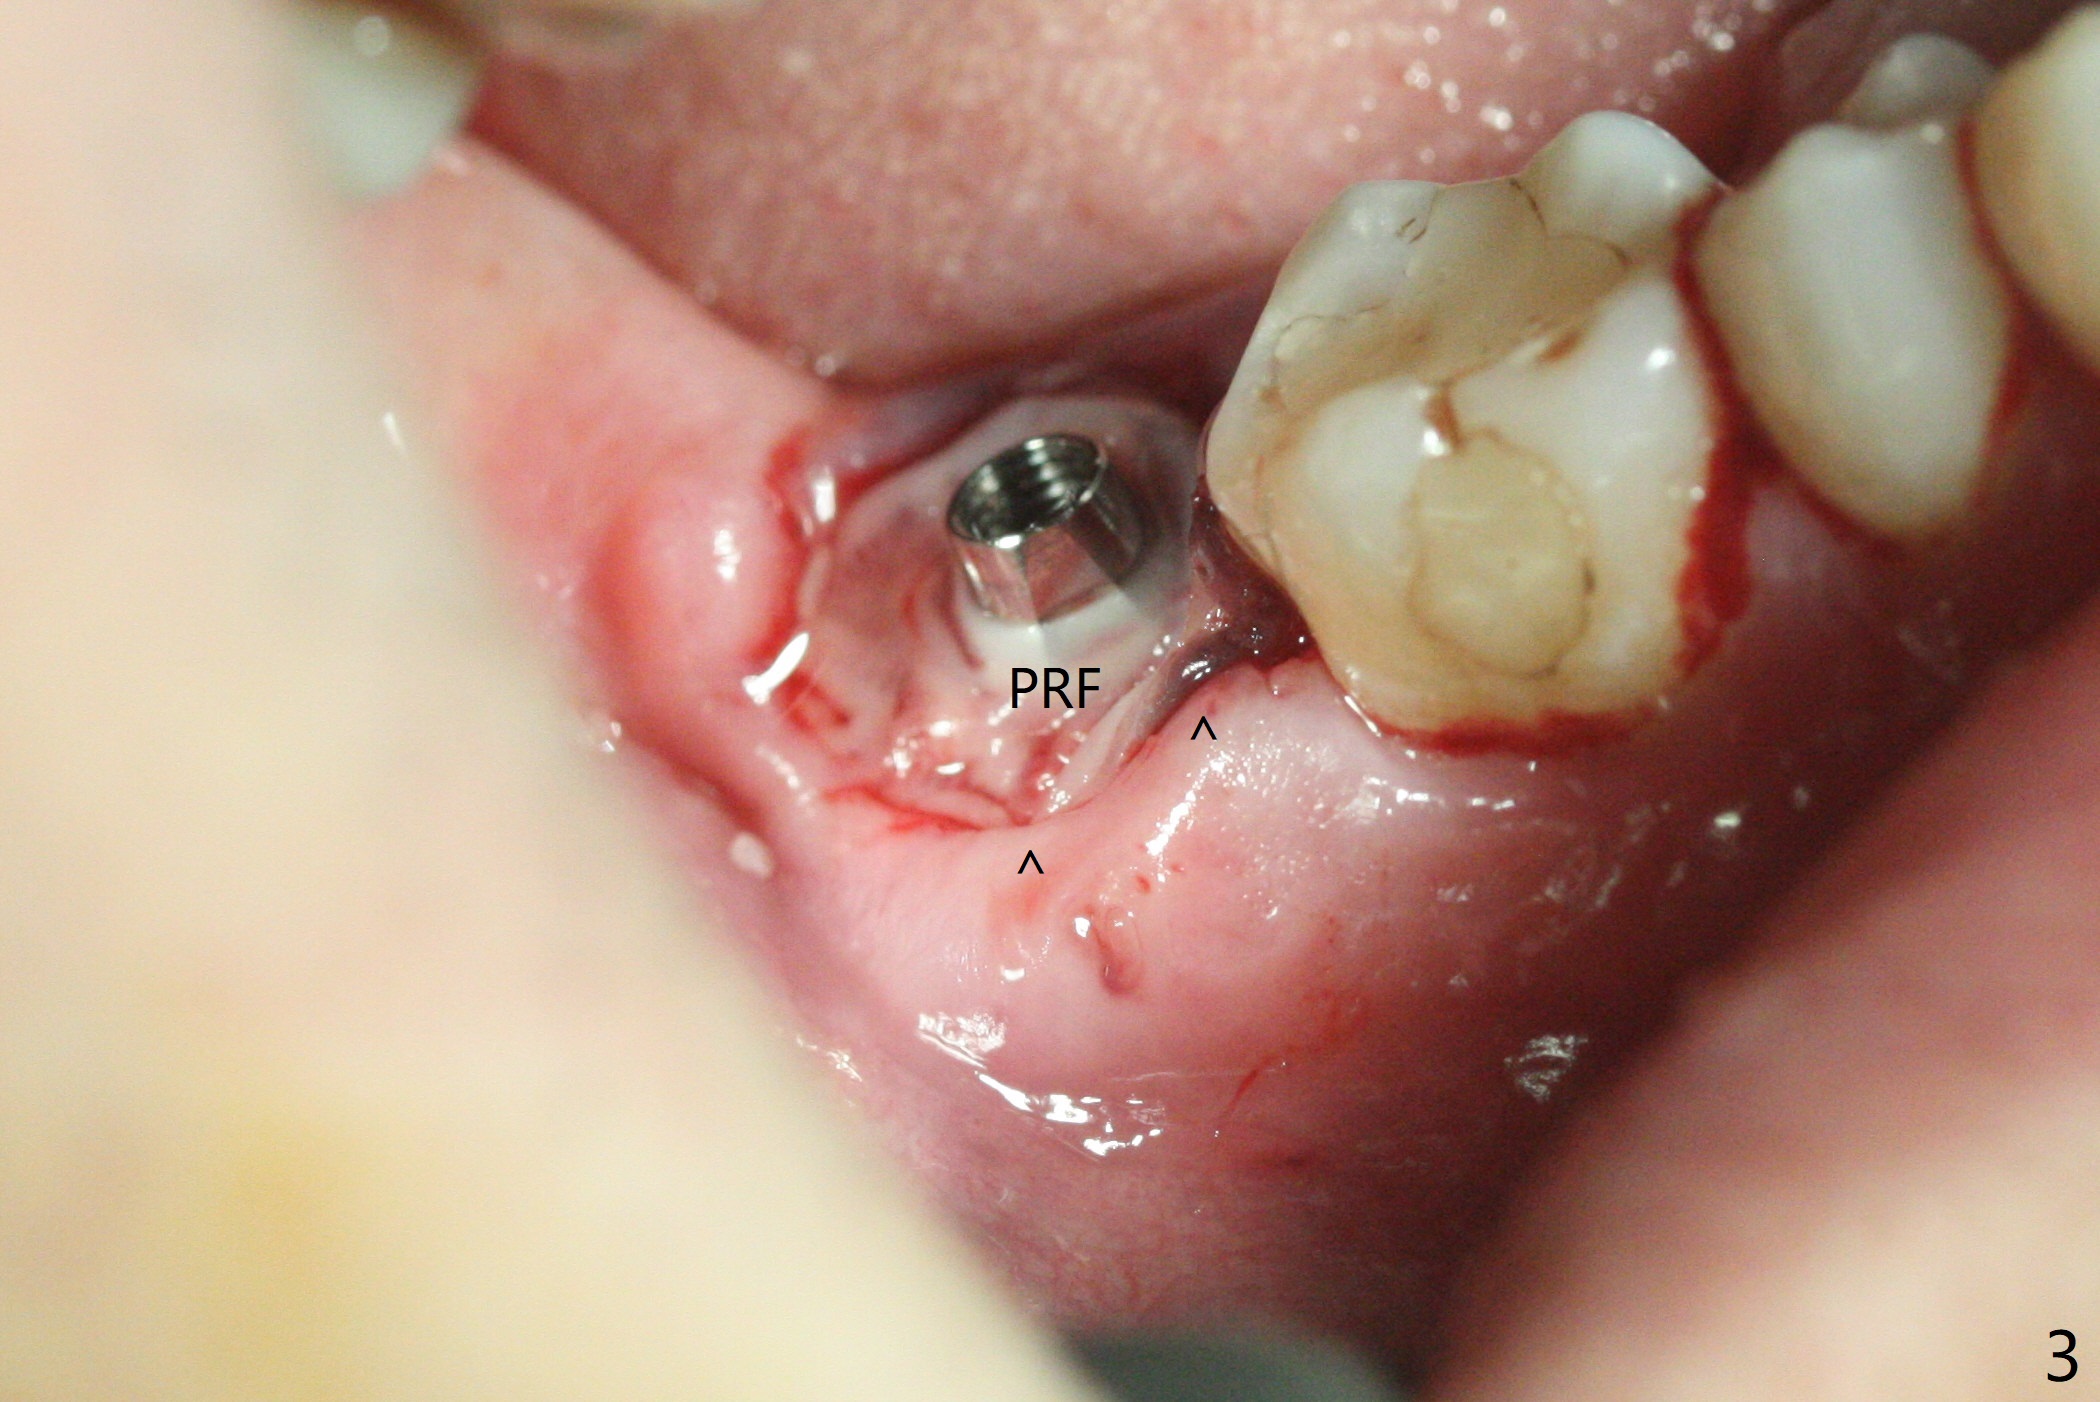

右下七5x11.5毫米植体导板植入根尖骨质大约2-3毫米(图一),扭力~50 Ncm,即使发生骨坏死,不会产生植体周围炎,最坏植体松动脱落。放置基台后,植入大量粘性骨粉(图二:*),覆盖PRF(图三);如果使用临时牙冠关闭牙槽窝,牙冠与龈缘(箭头)接触不紧,使用水牙线冲洗,骨粉流失严重。所以采纳树脂敷料(图四:A),后者边缘至少覆盖牙槽窝口1-2毫米,一周复查,及时关闭术后牙龈退缩所造成的漏洞。其实病人术后第二天回来,敷料脱落,理由:远中无牙,基台短(图五)。Return to Prevent Molar Periimplantitis (Protocols, Table) Protect Graft Torque 第一磨牙即种 Xin Wei, DDS, PhD, MS 1st edition 04/27/2021, last revision 04/29/2021